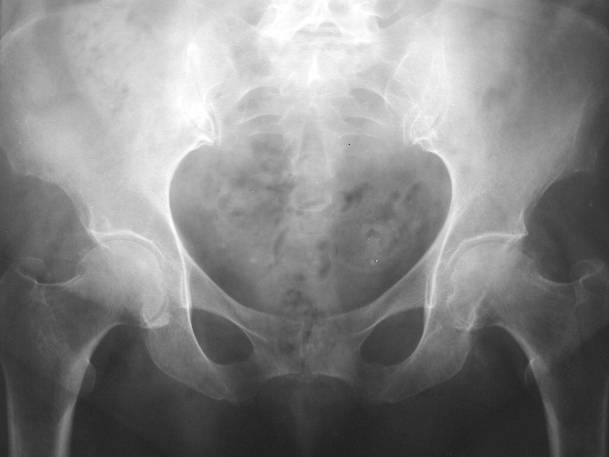

Chondrocalcinosis